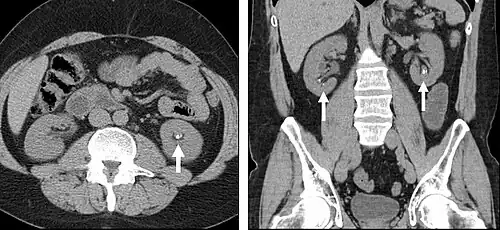

Portal venous phase

The most common technique is to perform portal venous phase imaging in the abdomen and pelvis (approximately 60–90 seconds after contrast administration, figure 2). This results in near optimal contrast opacification of the majority of the solid abdominal organs and it is used for a wide variety of indications: nonspecific abdominal pain; hernia; infection; masses (with a few exceptions such as hypervascular, renal, and some hepatic tumors); and in most follow-up examinations. As a general rule, this single phase is adequate unless there is a specific clinical indication that has been shown to benefit from other phases.

-

FIGURE 2. Contrast enhanced CT demonstrating parenchymal enhancement of the intra-abdominal organs in the portal venous phase (axial left, coronal reformat right).